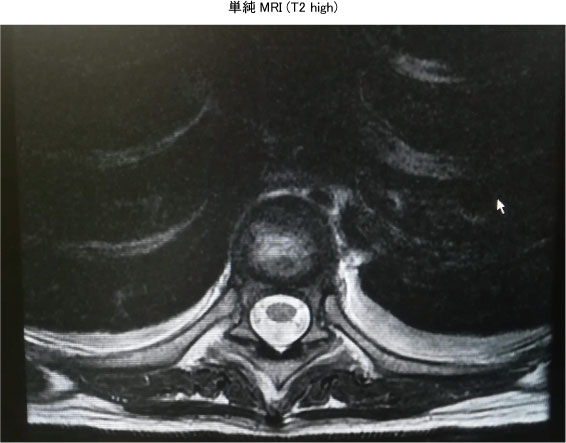

<‰æ‘œŠŒ©>

@E“–“úF¶—DˆÊ‚Ì‹¹…

@E8“úŒãF¶‹¹…